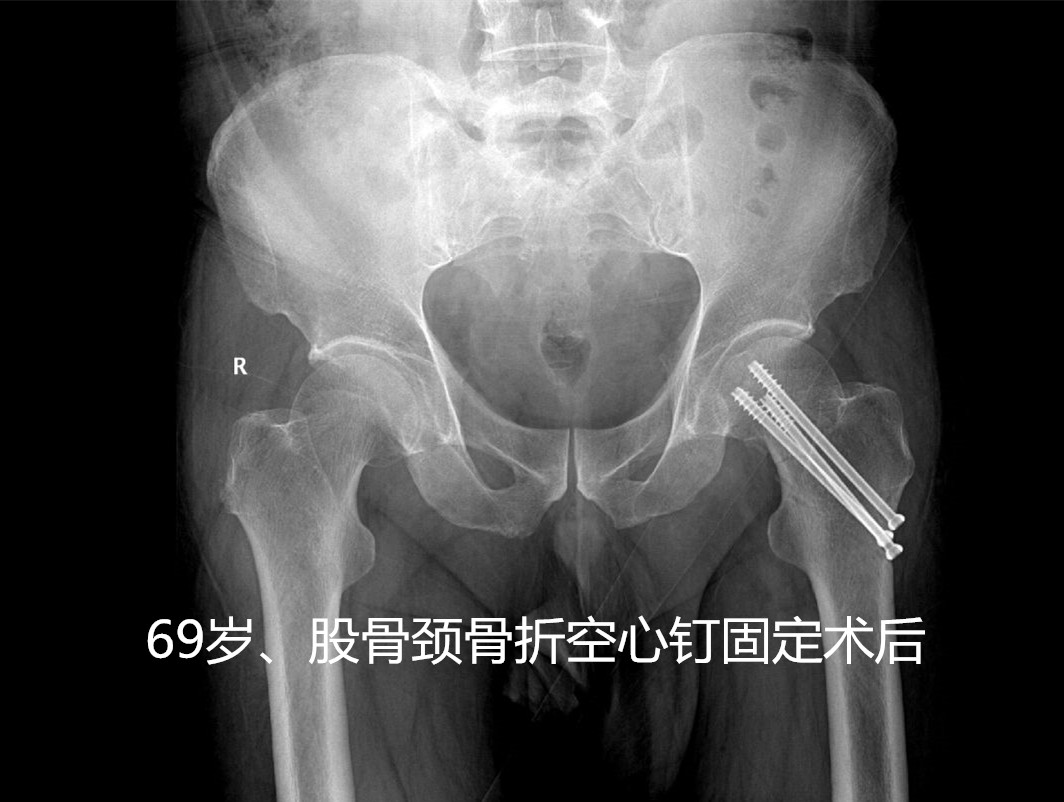

这种骨折出现了怎么治疗呢?其治疗方法分为手术内固定治疗(如空心钉、PFNA、INTER- tan等等)或者人工关节置换手术治疗。

- 对于无移位的股骨颈骨折,可保守治疗,但只要能耐受手术,无绝对手术禁忌症,还是建议手术治疗(如空心钉固定、手术创伤小、费用低),以免卧床期间出现骨折移位,减少卧床时间,便于护理。